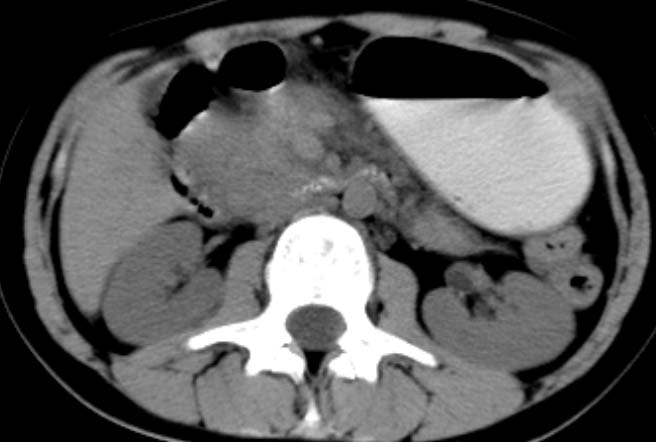

女,14岁。腹痛3天。腹部触诊未触及包块。碘剂阳性未增强。求助战友。。。。。。。。。。。

胰头部明显肿大,胰周间隙浸润,考虑胰腺炎可能性大

胰头部增大,周围模糊,有渗出,胰腺炎可能性大,建议结合化验检查;左侧输尿管上段略扩张.

胰头部明显肿大,胰头周脂肪密度加大。十二指肠环扩大受压。胰管未见确切扩张。考虑胰腺炎可能性大。建议增强扫描。

胰头部增大,周围结构模糊,并明显见渗出。支持:急性胰腺炎!

1)急性胰腺炎。2)肝右叶后上段肝内胆管结石。3)左侧输尿管上段扩张,原因待查。

病灶应在胰头下区,不一定是胰头,结合周边低密度水肿,是否可能为十二指肠(xi)室炎症或其它炎症。

胰周无明显渗出,吉氏筋膜未见增厚。血尿试验室检查不支持。排除胰腺炎。